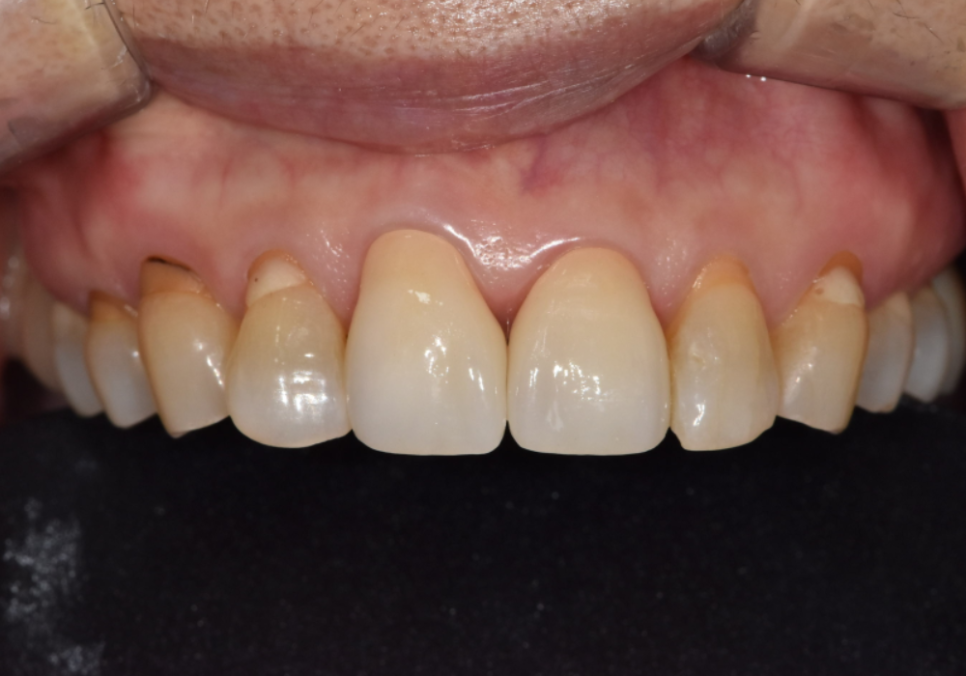

251229 (전) 260114(후)

이번 환자분 역시 옆 치아와 이질감이

전혀 느껴지지 않도록

자연스러운 지르코니아로 완성해 드렸습니다.^^

260114